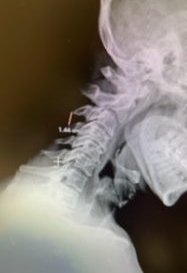

(2a) Lateral Flexion cervical x-rays demonstrating 8mm of splaying of the C34 interspinous distance

(2b) Lateral Flexion cervical x-rays extension image demonstrating 8mm of splaying of the C34 interspinous distance.

The fluid was possibly consistent with CSF versus chronic hematoma. The patient was also noted to have a high signal within the interspinous space of C3-C4. This high signal was consistent with a ruptured C3-4 interspinous ligament. Cervical flexion-extension x-rays demonstrated 6 mm of widening of the C3-4 interspinous space on flexion x-ray consistent with cervical instability (Fig. 2a and 2b).